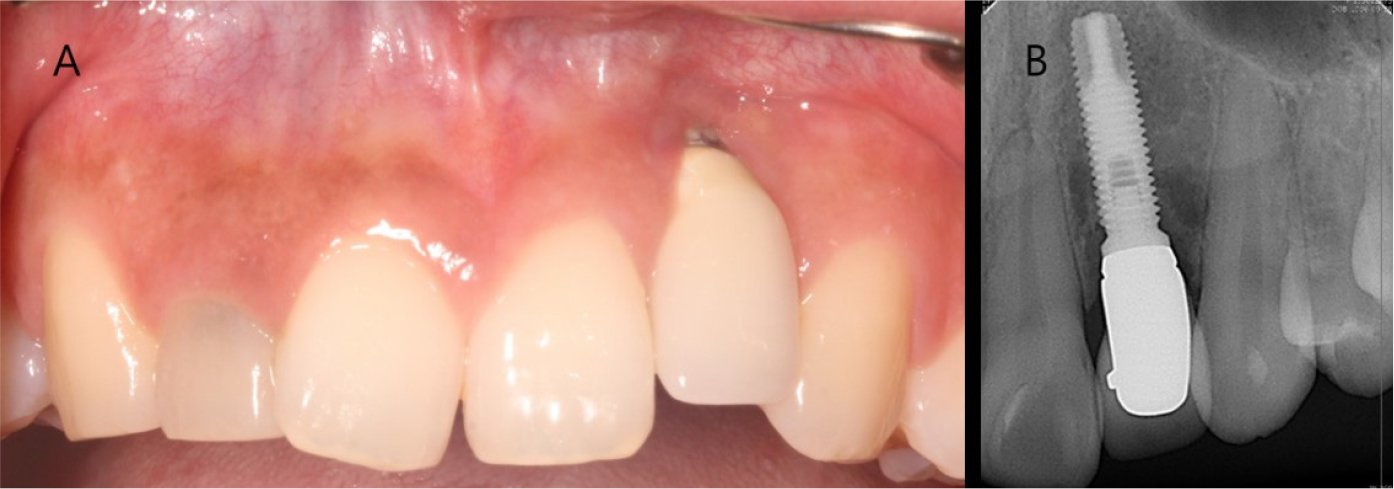

A 26-year-old woman complained of gingival recession around a maxillary anterior implant restoration. The patient had a splinted restoration with 3 implants in the maxillary anterior region placed immediately after tooth extraction (#12, #11, and #21) because of root fracture 2 years before. Bone or soft tissue grafting was not performed according to the patient interview. Clinical examination revealed gingival recession around the implant restoration in the right maxillary lateral incisor region, exposed zirconia abutment, and a gray fixture below the gingiva. A deep periodontal pocket and thin periodontal biotype were observed on the buccal side (Fig. 1).